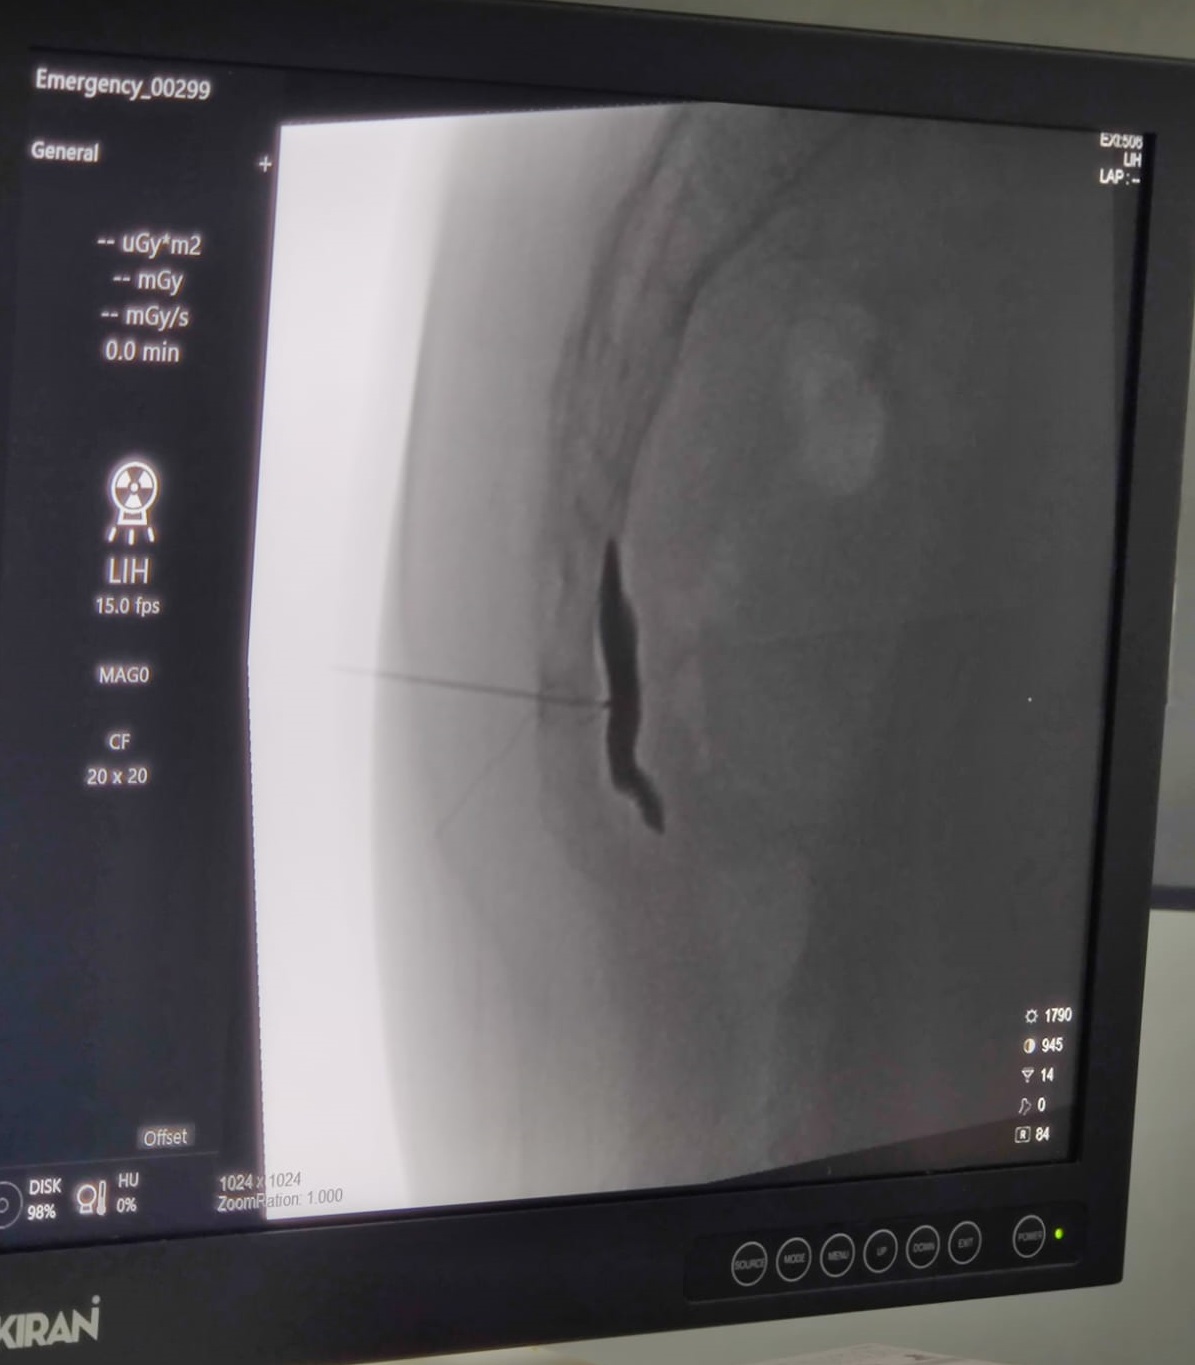

Ganglion Impar Radiofrequency neurectomy is an advanced procedure which involves the precise placement of the Radiofrequency needle just anterior to the Sacro-coccygeal junction, identification of the ganglion with the help of sensory and motor stimulation and then its targeted ablation using Radiofrequency current.

To see how this procedure is done, click the below link